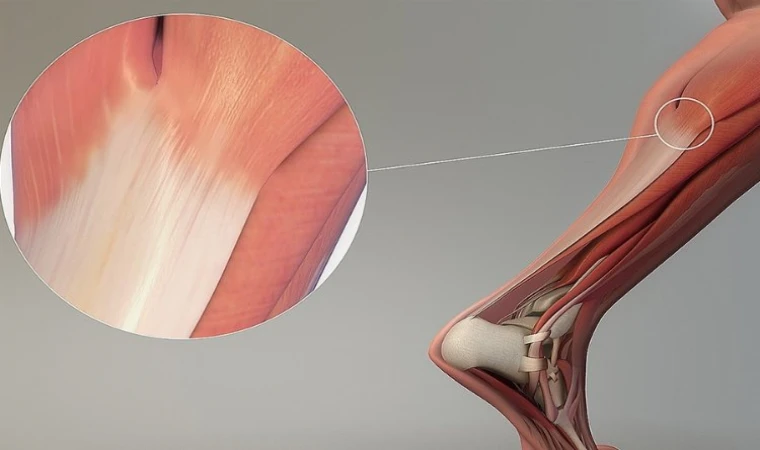

TENDON YARALANMASI

Ortopedi ve Travmatoloji Uzmanı Prof. Dr. Metin Uzun, yaz aylarında spor yaparken en sık oluşan sakatlanmalardan tendon yaralanmasını anlatarak önemli öneriler ve uyarılarda bulundu.

Kasları kemiğe bağlayan sert yapılar “tendon” olarak adlandırıldığını kaydeden Prof. Dr. Metin uzun, "Tendonlar çok güçlü yapılar olmakla beraber; en sık ani yapılan hareketler sırasında yaralanabiliyor. Biceps tendonu ve aşil tendonu en çok yaralanan tendonlar arasında yer alıyor. Tendon yaralanmalarının her yaşta ve düzenli spor yapan herkeste gelişebiliyor. Tendon yaralanmaları genellikle spor öncesinde yeterli esneme ve ısınma hareketi yapmayanlar veya spor sırasında yorulmalarına rağmen ‘Son anlar veya son tekrarlar, nasıl olsa bir şey olmaz’ diyerek devam eden kişilerde, spor sonunda oluşur” dedi.

Aniden gelişen ağrı ve bacaklardaki şekil bozukluğunun tendon yaralanmalarının ilk belirtileri olduğunu vurgulayan Prof. Dr. Metin Uzun, “Özellikle aşil tendonu kopan kişiler sıkıntılarını ‘Biri ayağıma vurdu’ veya ‘Taş attılar zannettim, etrafıma baktım ne taş vardı ve ne de birisi’ şeklinde tanımlarlar” dedi.

İyileşme süresinin sakatlığın bulunduğu bölgeye göre 6 hafta ile 3 ay arasında değiştiğini belirten Uzun, “Aşil tendon yaralanmalarında bu sürenin ilk 3 haftası evde istirahat ile geçmektedir. Hastalar 3. haftadan sonra desteksiz yürüyebilir hale gelirler” dedi. Uzun, bunu önlemek için spor öncesinde ve sonrasında esneme hareketleri yapmayı alışkanlık edinilmesini istedi.